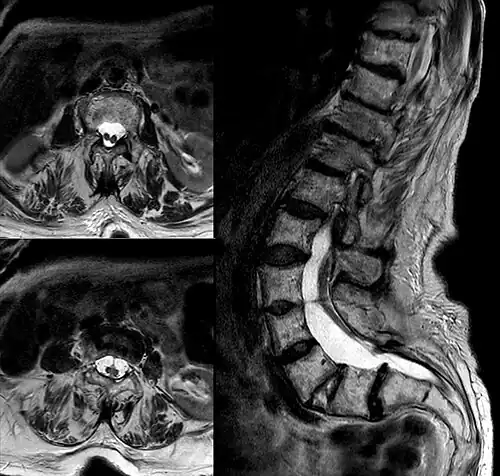

Diastematomelia in MRI of lumbar spine.

In neurology, diastematomyelia (occasionally diastomyelia) is a congenital disorder in which a part of the spinal cord is split, usually at the level of the upper lumbar vertebra in the longitudinal (sagittal) direction. Females are affected much more commonly than males. This condition occurs in the presence of an osseous, cartilaginous or fibrous septum in the central portion of the spinal canal which then produces a complete or incomplete sagittal division of the spinal cord into two hemicords. When the split does not reunite distally to the spur, the condition is referred to as diplomyelia, which is true duplication of the spinal cord.[1]